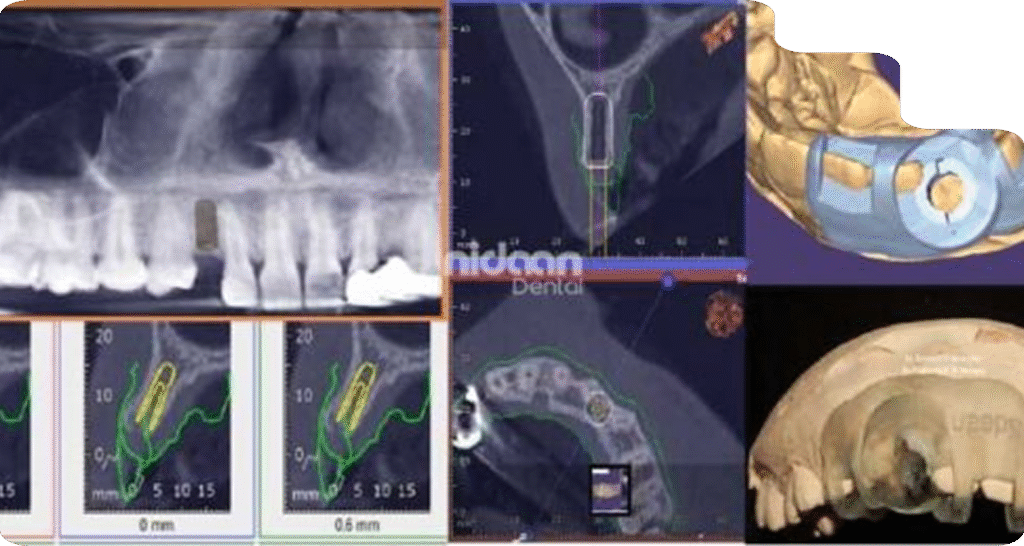

Virtual implant planning & Guide Designing